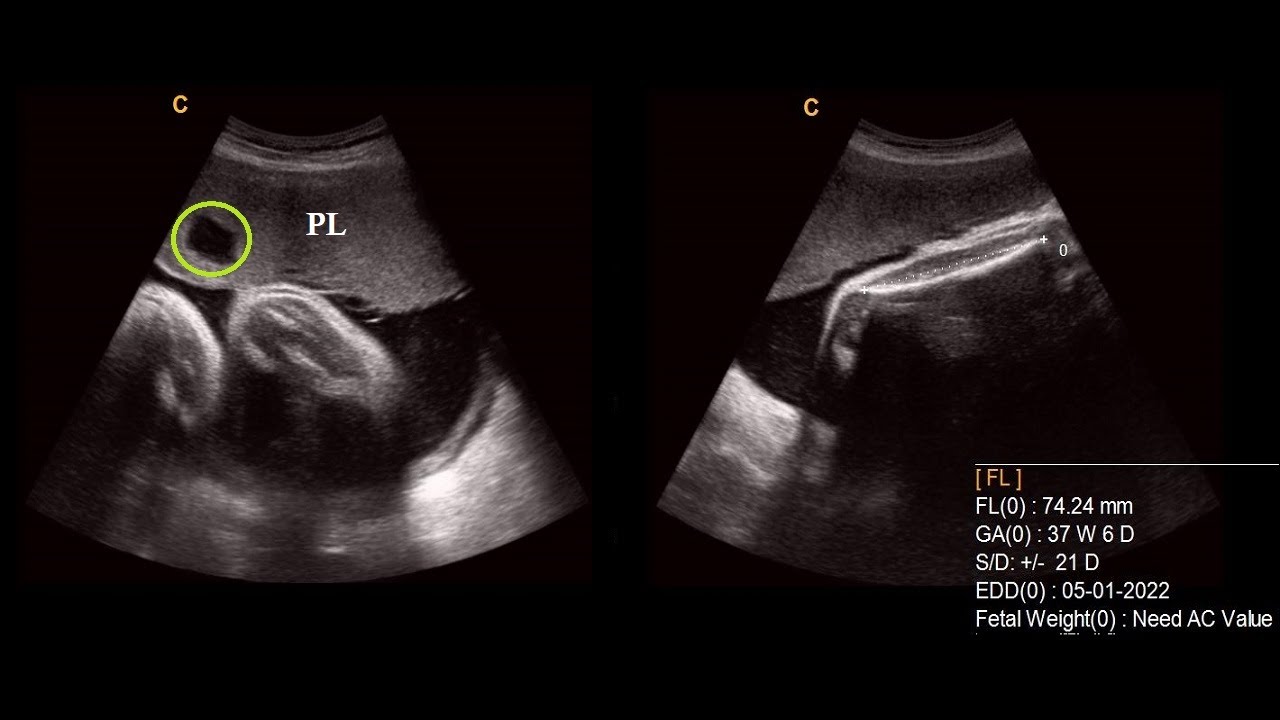

Multiple placental lakes 38 weeks pregnancy Pregnancy Profile What Is Placental Lakes They are so common that it's. Placental lakes are seen on ultrasounds as black areas on the surface or deeper inside the placenta, and are actually. Finding placental lakes during a second trimester. These spaces are also called intervillous spaces. They lie on the surface of the placenta or deeper inside. They are defined at the mid. They show up. What Is Placental Lakes.

What Is Placental Lakes . They lie on the surface of the placenta or deeper inside. Placental lakes are pools of blood that show up on scans as black areas. What is the significance of a placental lake? Placental lakes are enlarged spaces in the placenta filled with maternal blood. Placental lakes are the most common placental feature seen on grayscale ultrasound. What is a placental lake? They show up on ultrasound scans as black areas. These spaces are also called intervillous spaces. They lie on the surface of the placenta or deeper inside. Finding placental lakes during a second trimester. They are so common that it's. What is a placental lake? Placental lakes are spaces within the placenta filled with maternal blood. Placental lakes are seen on ultrasounds as black areas on the surface or deeper inside the placenta, and are actually. They are defined at the mid.

Placental lakes are enlarged spaces in the placenta filled with maternal blood. Placental lakes are spaces within the placenta filled with maternal blood. Placental (venous) lakes refer to a phenomenon of formation of hypoechoic cystic spaces centrally within the placenta. What is a placental lake? They show up on ultrasound scans as black areas. They lie on the surface of the placenta or deeper inside. They are so common that it's. Placental lakes are pools of blood that show up on scans as black areas. They are defined at the mid. They lie on the surface of the placenta or deeper inside.